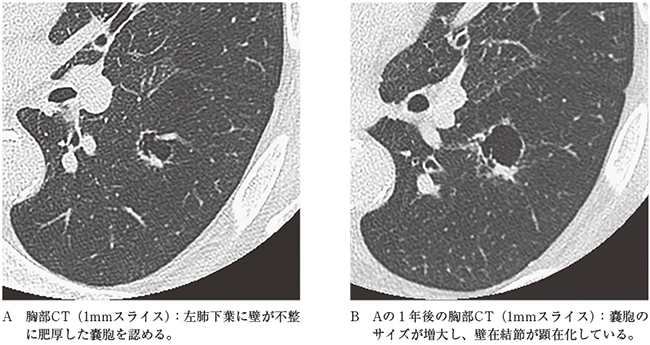

4)嚢胞状

単純X線よりCTで問題となることの多い所見である。肺癌と診断された病変を過去に遡ってみると嚢胞状を呈していることはまれではない。肺癌CT検診での解析では、最初に見逃された癌の22%が嚢胞に関連していたと報告されている5)。そのような状況を踏まえ、American College of Radiologyが低線量肺癌検診のガイドラインとして提唱しているLung CT Screening Reporting and Data System (Lung RADS)では、atypical pulmonary cystが肺癌の可能性のある嚢胞として2022年版より記載されている。Atypical pulmonary cystには壁の厚い(2mm以上の)嚢胞、多房性嚢胞、壁在結節を伴う嚢胞が該当し、経過観察等の対応をとるように推奨されている(図5A,B)。壁の薄い(2mm未満の)嚢胞は精査や経過観察の対象とはされていない6)。

図5 60歳代男性。充実型腺癌。